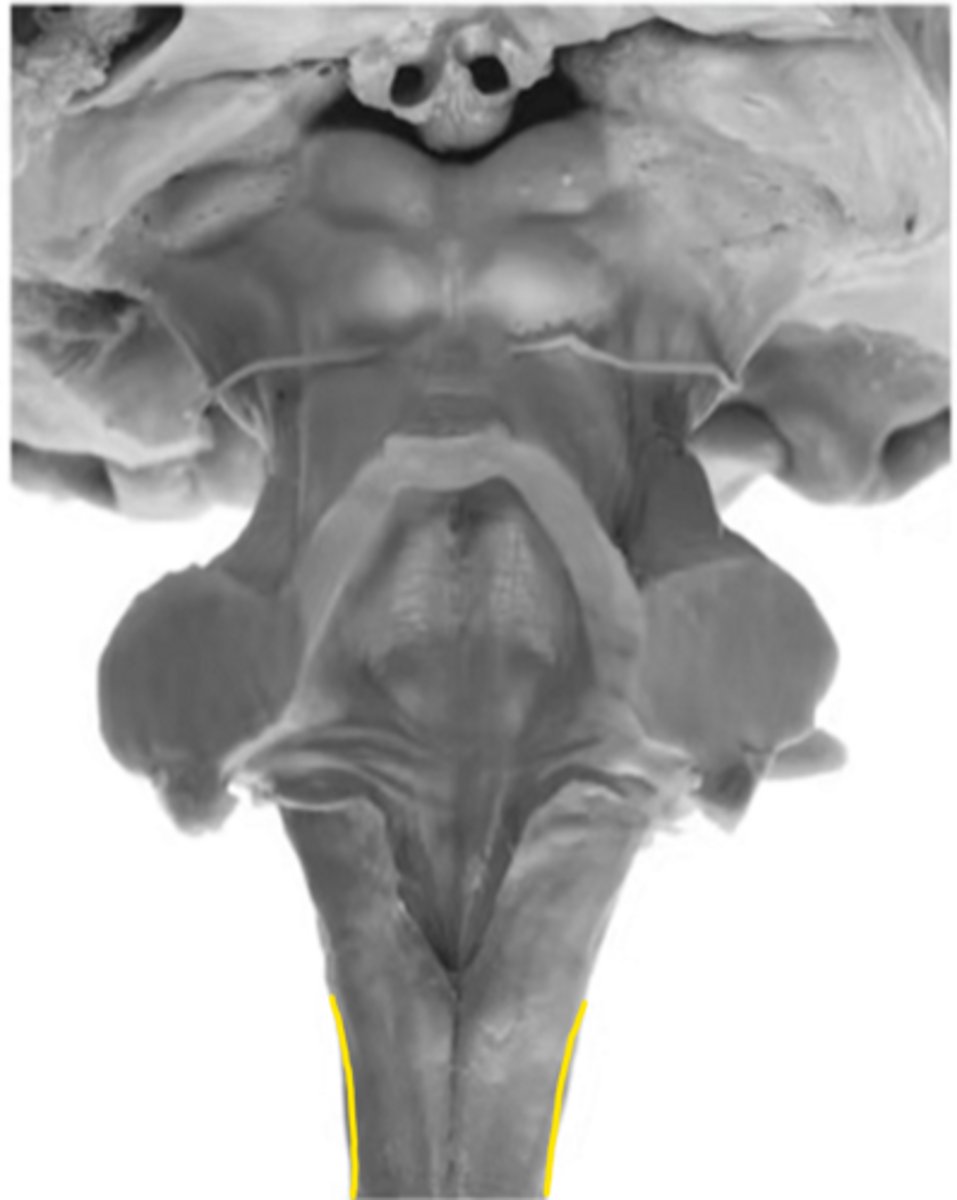

motor decussation

ID the structure